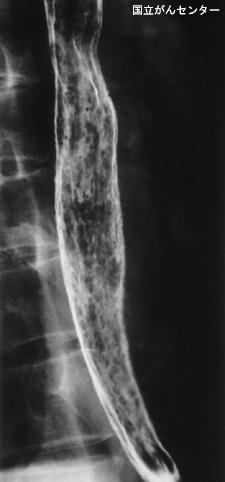

Candidiasis de Esófago originario de cáncer avanzado del estómago

Tokyo Pref., Centro Nacional de curaciones de Cáncer, Hospital Central y Centro Kyusyu de Curaciones de Cáncerc

Enfermedad Inflamatoria - Ulcerativa/Esofagitis moniliásica

esófago/mas de dos

Rayos X

1 - 9